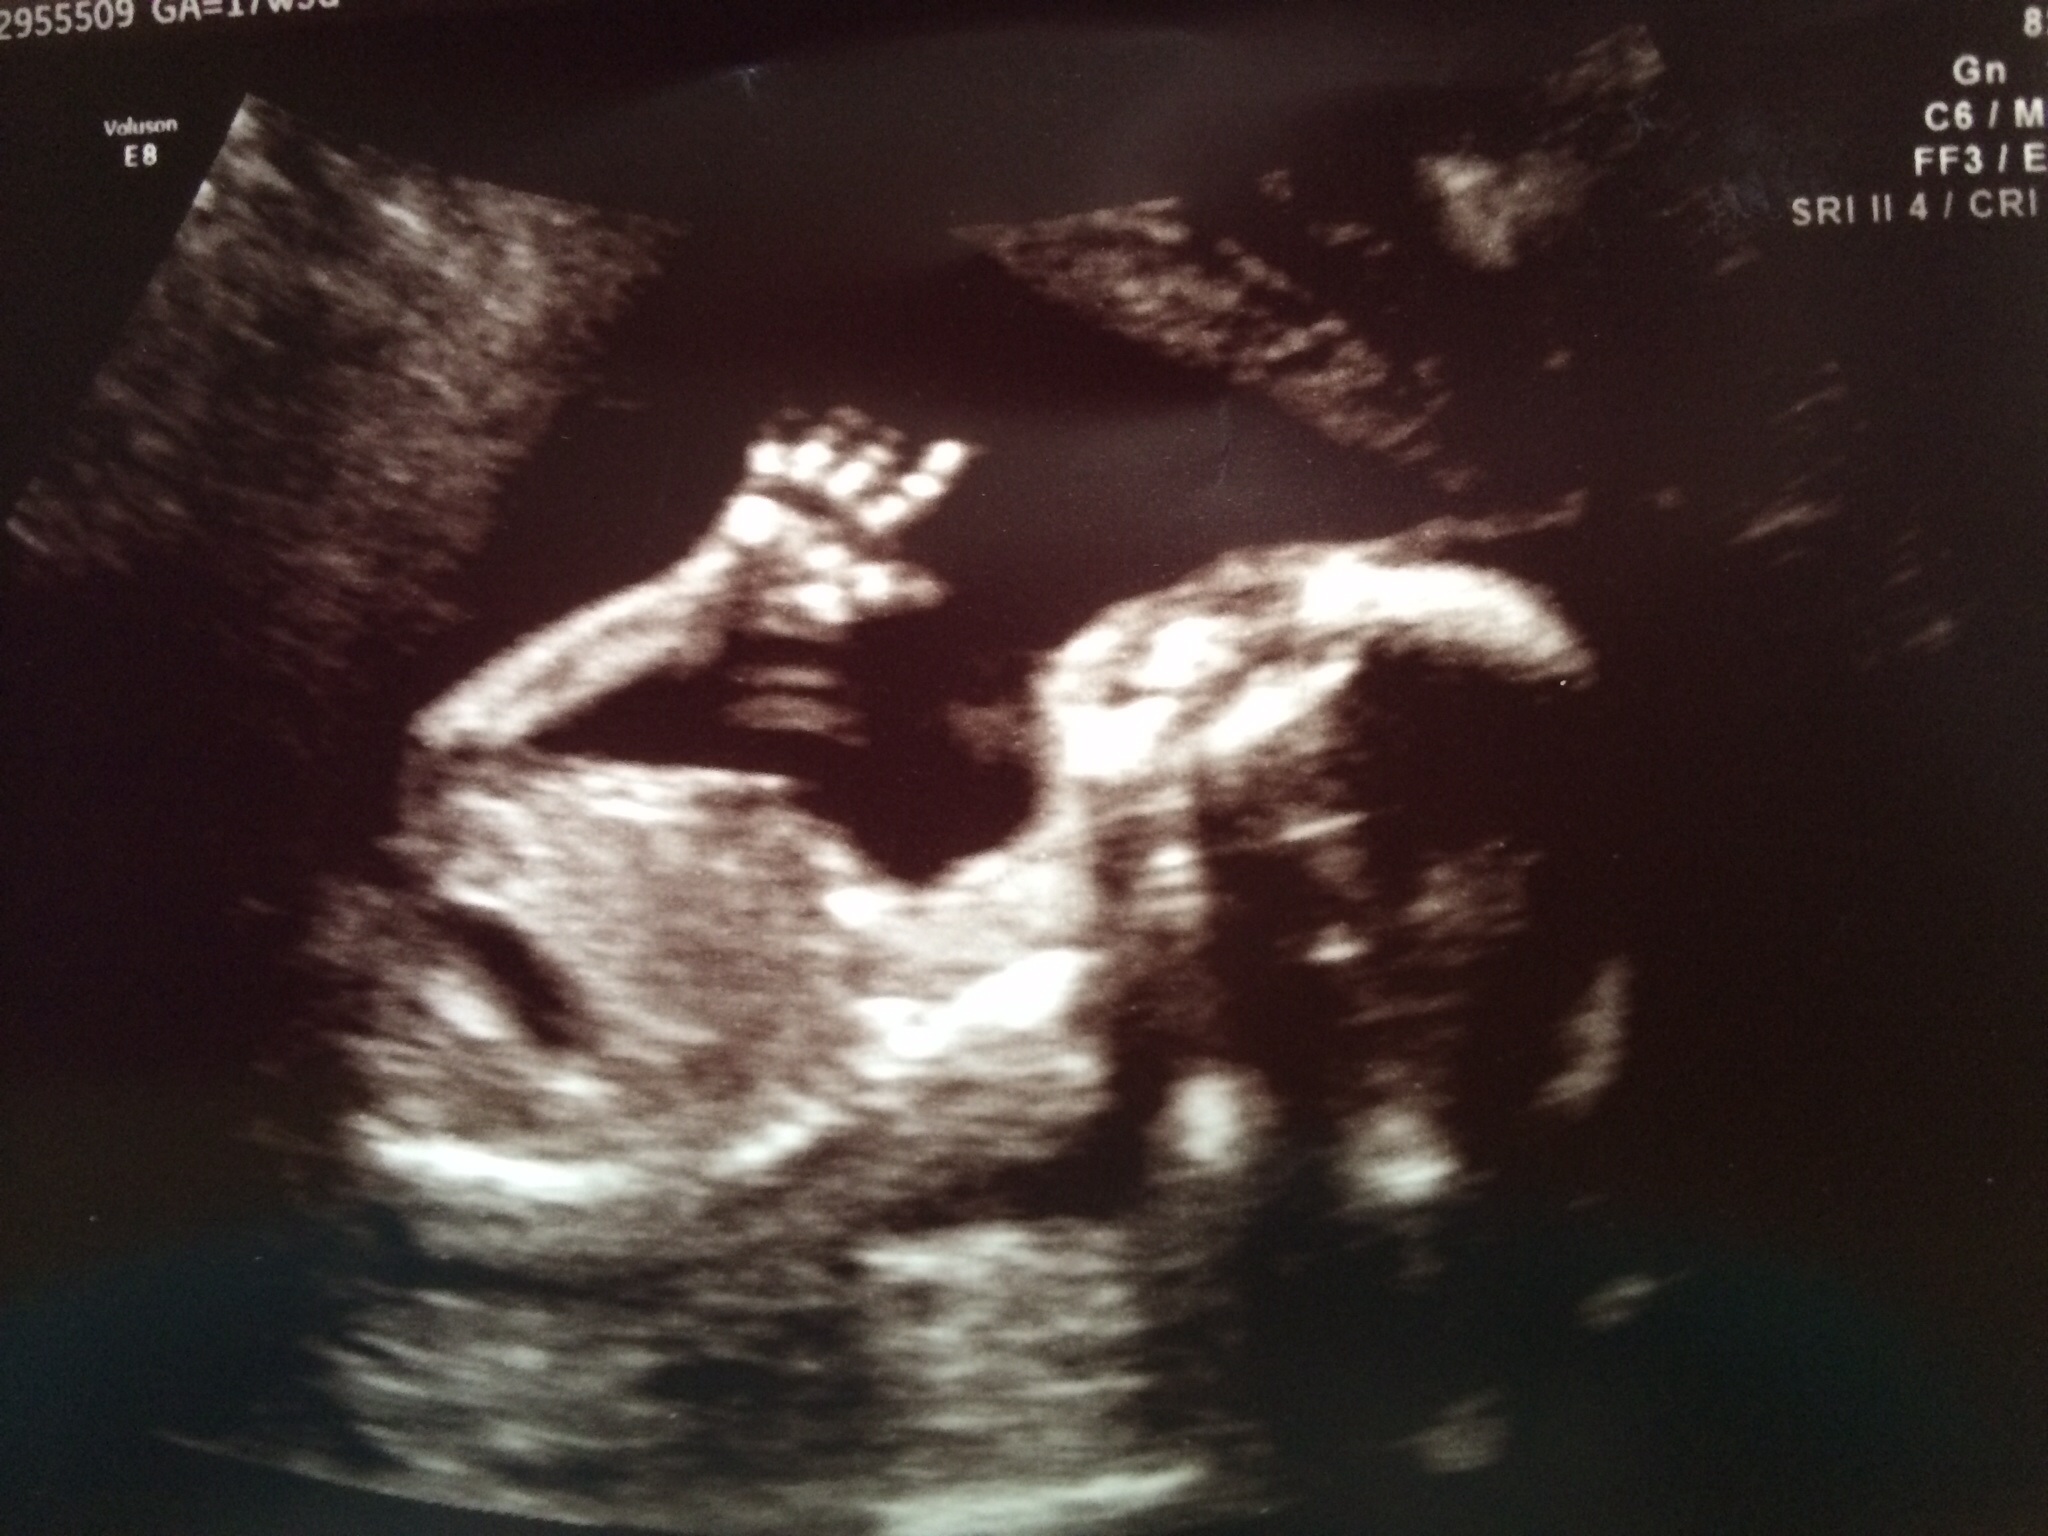

I`m freaking out... PGAL brain kills me. I don`t know how I`m going to sleep this night.

image

BabyFruit Ticker

imageimageimage

Baby# 1 - gone at 6 weeks - Oct 2009

Baby# 2 ( beloved girl Maria) -stillbirth at 31 weeks - Apr 2013

Baby# 3 EDD April 2014 - Hope it`s our take home baby

*sorry for grammar mistakes, I learned english pretty much by myself.